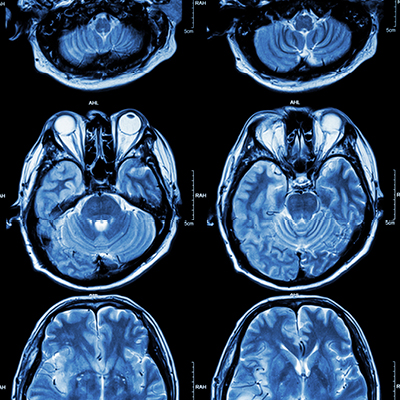

According to the CDC, someone in the US has a stroke every 40 seconds. Those patients who receive emergency care greatly increase their rate of survival and shorten recovery time. A stroke occurs when blood supply is reduced or cut off from the brain, and that root cause is sometimes due to a blood clot.

When a patient comes in and is diagnosed with a stroke, medications can be administered intravenously to break up and restore blood flow back to the brain. However, this medication is only successful around 25 percent of the time when used on large blockages. In these cases, recent advances in technology have opened the door to another treatment option.

If the blockage is not removed quickly, the lack of oxygen to the brain can cause permanent damage to healthy brain cells and lead weakness, paralysis or other permanent disability.

A thrombectomy is a minimally invasive procedure used to remove a blood clot in the brain. This procedure uses a small intravenous device - like a catheter - to remove the obstruction. The device is guided by visual imaging - like a camera or to locate the blockage and monitor the surrounding tissue for blood flow. The catheter travels through an artery through a very small incision in the groin area. The goal is to get the retrieval device past the blood clot. Once there, a small balloon attached to the catheter’s tip will inflate. The catheter is then slowly pulled back and removed, bringing the balloon and the blockage out with it. This immediately restores blood flow back to the brain.